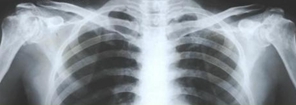

重视理论联系实际是学好医学影像学的关键。应重视实训教学和实践操作,在实践中逐步培养自己分析、综合解决问题的能力。应多看图片、多看病例,设法搜集病例资源注意观察阅读正常影像表现,培养对异常影像表现的辨别能力及描述能力,注重实习报告的书写等基本功训练,书写报告时要求达到认识准确,语言精炼,并有分析鉴别,从而达到科学性、逻辑性、客观性。